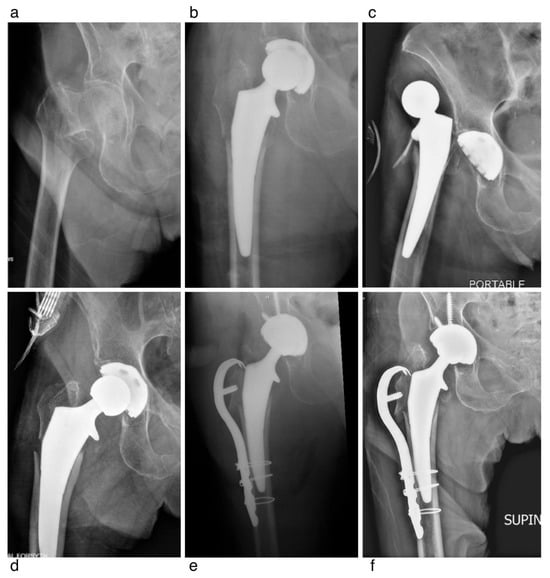

A Modern Collared Cementless Femoral Stem for the Arthroplasty Treatment of Femoral Neck Fractures

Background/Objectives: For femoral neck fractures (FNFs) treated with hip arthroplasty, cemented femoral fixation is frequently recommended due to its association with reduced early perioperative fracture and reoperation rates. However, newer-generation collared, cementless triple-tapered (CCTT) stems may present benefits compared with conventional press-fit designs. This study sought to assess 30-day survivorship of a CCTT stem in patients undergoing hip arthroplasty for FNF via the direct anterior approach (DAA). Methods: We conducted a retrospective review of all patients who underwent hemiarthroplasty (HA) or total hip arthroplasty (THA) for displaced FNF from 2019 to 2023. All procedures were performed through the DAA using a hydroxyapatite-coated CCTT femoral stem. The primary outcome was 30-day stem survival. Secondary outcomes included reoperation, stem revision, complications, readmission, and radiographic outcomes including intraoperative and postoperative periprosthetic fracture and subsidence. Results: A total of 184 patients were included (mean age 76.1 ± 10.0; 70.1% women). THA was performed in 77.7% and HA in 22.3%. At 30 days, no stems required revision. The 30-day reoperation rate was 3.5% (5/184). There were four intraoperative fractures: 3 (1.6%) Vancouver AG and 1 (0.5%) calcar. Postoperatively within 3 months, seven fractures occurred: five (2.7%) Vancouver AG and two (1.1%) Vancouver B1. Conclusions: Use of a modern CCTT femoral stem for FNF demonstrated excellent early survivorship with low rates of intraoperative and postoperative periprosthetic fracture, comparable to published outcomes of cemented fixation. These findings suggest that this stem design may represent a safe and efficient alternative to cemented femoral fixation in FNF. Further studies are warranted to evaluate mid- and long-term outcomes. Full article

Show Figures

Figure 1